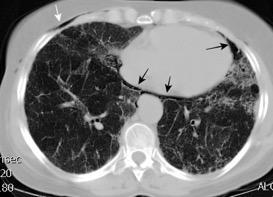

Nódulos pulmonares múltiples. (flechas verdes). Masas paratraqueales. (flechas amarillas). Dudoso ensanchamiento retrocrural (flechas negras). sigue….

Ttawfik A et al. Trans-diaphragmatic Pathologies: Anatomical Background and Spread of Disease on cross-sectional Imaging. Current Problems in Diagnostic Radiology. 2021.

T. mixto de células germinales del testículo

izquierdo Metástasis pulmonares. (flechas verdes). Ganglios paratraqueales. (flechas amarillas). Ganglios retroperitoneales (flechas negras)

Tawfik A et al. Trans-diaphragmatic Pathologies: Anatomical Background and Spread of Disease on cross-sectional Imaging. Current Problems in Diagnostic Radiology. 2021.